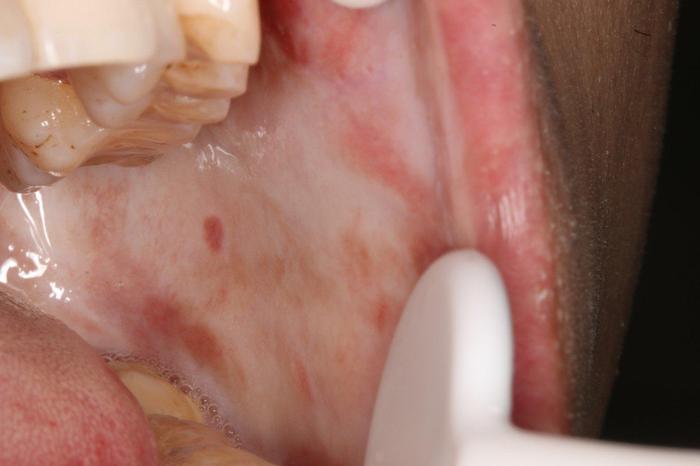

口腔黏膜纤维化

吃槟榔口腔纤维化图片 口腔纤维化图片

什么是口腔黏膜纤维化,看完还敢嚼槟榔吗?